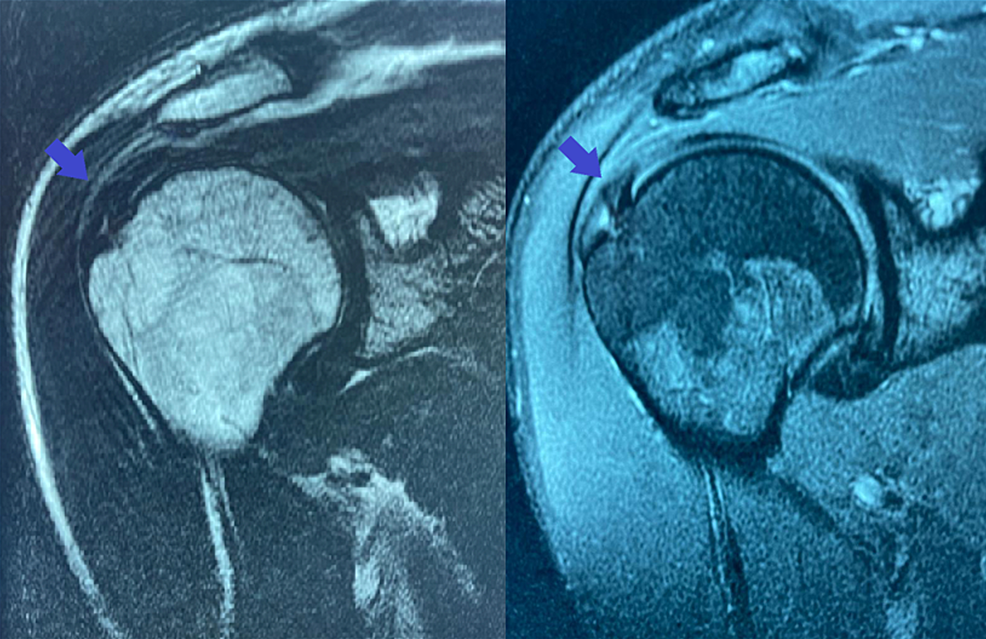

From www.cureus.com

Cureus UltrasoundGuided Injection of a Hyaluronic Hyaluronic Acid Injection Rotator Cuff The use of ha in patients with rotator cuff tears improve vas and functional score in all trials that we have analyzed. The present study demonstrated that pain and shoulder function were improved significantly after sh treatment. A combined injection of hyaluronic acid and prp (weekly × 4 weeks) into the subacromial space was found to significantly. Hyaluronic Acid Injection Rotator Cuff.

UltrasoundGuided Injection of a Hyaluronic Acid Hyaluronic Acid Injection Rotator Cuff The present study demonstrated that pain and shoulder function were improved significantly after sh treatment. The use of ha in patients with rotator cuff tears improve vas and functional score in all trials that we have analyzed. A combined injection of hyaluronic acid and prp (weekly × 4 weeks) into the subacromial space was found to significantly. Hyaluronic Acid Injection Rotator Cuff.

From www.researchgate.net

(PDF) UltrasoundGuided Injection of a Hyaluronic Hyaluronic Acid Injection Rotator Cuff A combined injection of hyaluronic acid and prp (weekly × 4 weeks) into the subacromial space was found to significantly. The use of ha in patients with rotator cuff tears improve vas and functional score in all trials that we have analyzed. The present study demonstrated that pain and shoulder function were improved significantly after sh treatment. Hyaluronic Acid Injection Rotator Cuff.

UltrasoundGuided Injection of a Hyaluronic Acid Hyaluronic Acid Injection Rotator Cuff The use of ha in patients with rotator cuff tears improve vas and functional score in all trials that we have analyzed. The present study demonstrated that pain and shoulder function were improved significantly after sh treatment. A combined injection of hyaluronic acid and prp (weekly × 4 weeks) into the subacromial space was found to significantly. Hyaluronic Acid Injection Rotator Cuff.